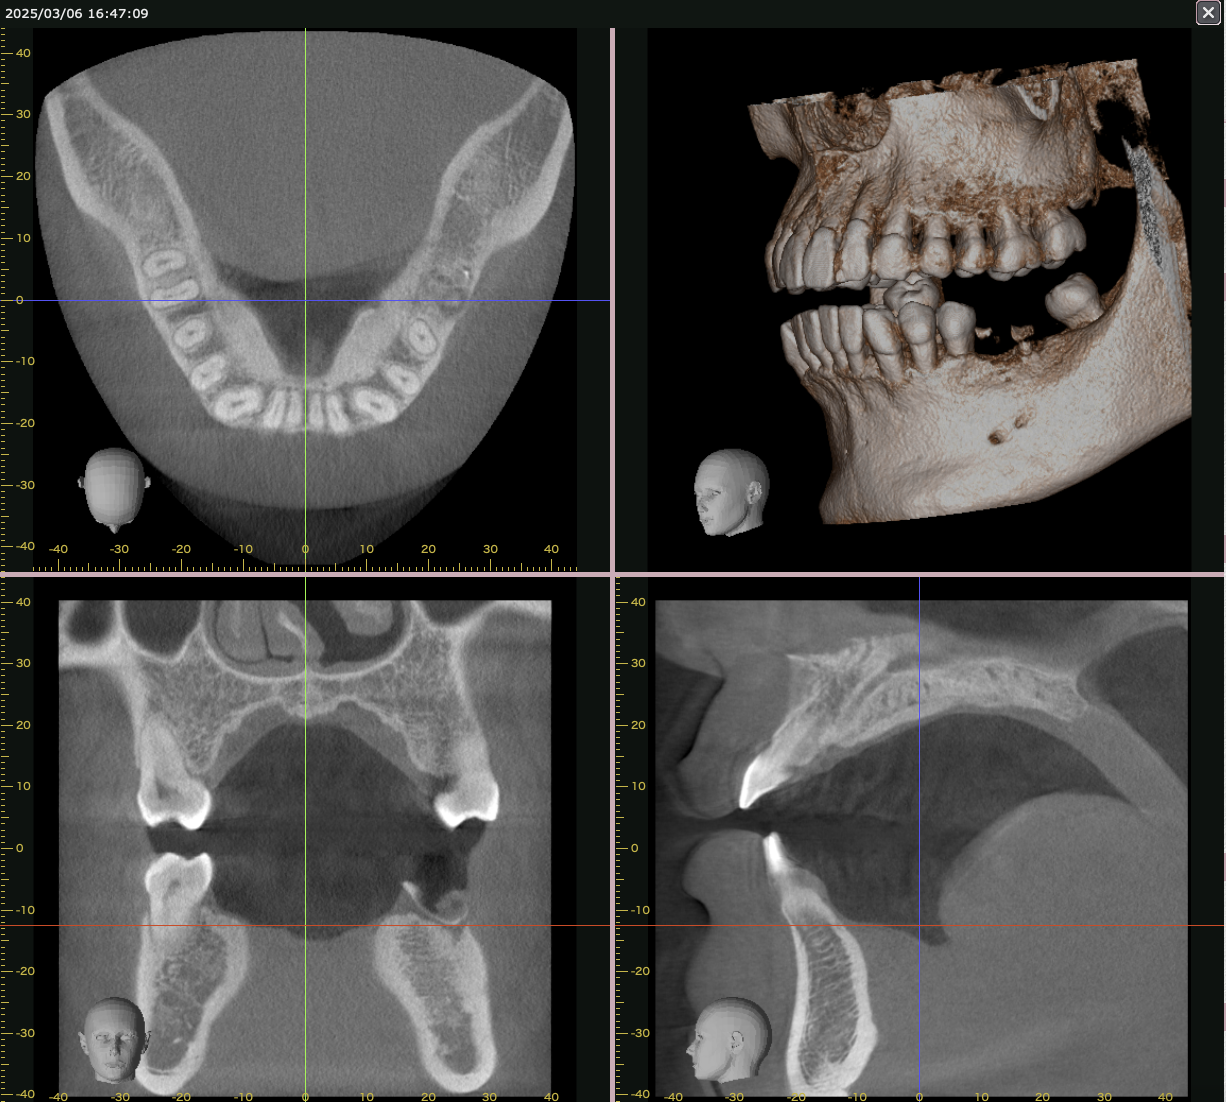

- CBCT撮影(骨の状態の把握)

- デジタル画像診断(将来の歯を想定し、インプラントの埋入計画を立体視)